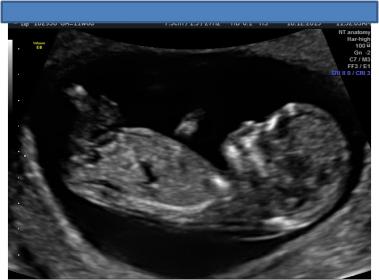

Ultrasound Guesses 12 week potty shot and nub

I know that potty shots are not accurate at this stage, however bub was not cooperative, and was upside down for most of the scan we really didn't get a good look at the nub. I have posted two shots, one is a potty shot and shows what looks like a very forked nub which is also what i saw in the ultrasound in the ultrasound however don't have an image of that particular shot of the baby. The second shot I am not even sure that is a nub as it is just not obvious to me - but posting it just in case.

Attachment 15761